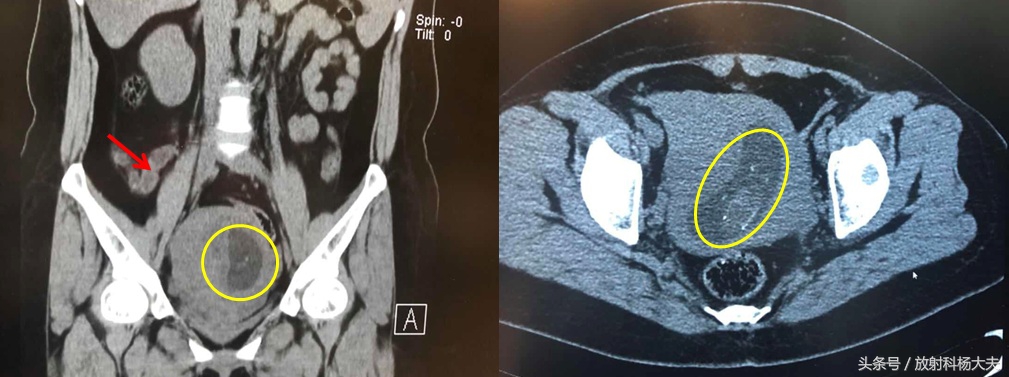

红箭为阑尾炎,黄圈为胎儿

这个女性,34岁,临床怀疑阑尾炎,因症状不典型,建议做CT,做CT前包括外科,放射科均询问是否怀孕,均肯定答复:没有。

结果CT做完了,阑尾炎确实存在,但同时发现了子宫内有胎儿!